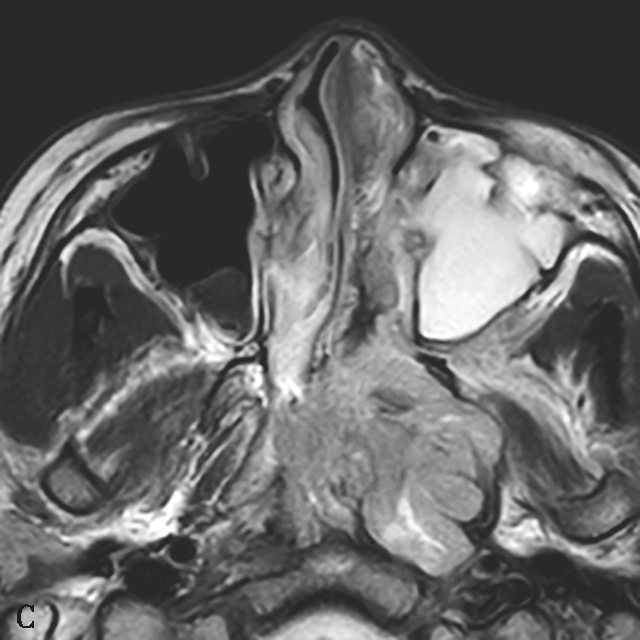

图1-2-4 青少年鼻咽纤维血管瘤

患者男,12岁,间断鼻出血1年。A.鼻窦CT横断面骨窗,示左侧蝶腭孔扩大,被不规则软组织肿块占据,病变累及左侧鼻腔、鼻咽、翼腭窝,邻近骨质可见溶骨性骨质破坏;B.鼻窦CT冠状面重组骨窗,示病变累及鼻腔、蝶窦,邻近骨质可见溶骨性骨质破坏;C.鼻咽部MR T 2 WI横断面,示左侧鼻咽、鼻腔不均匀等信号肿块,病变通过扩大蝶腭孔累及翼腭窝,病变内可见多发血管流空信号;D.鼻咽部MR T 1 WI横断面,示病变呈不均匀低信号;E.鼻咽部MR T 1 WI横断面增强+脂肪抑制序列横断面,示病变显著不均匀信号,与邻近组织分界尚清